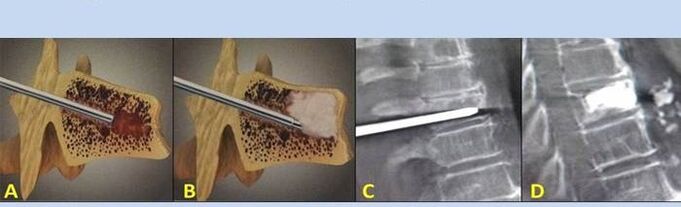

- Nükleoplasti – intervertebral diskin çekirdeğinin çıkarılması. Operasyon sinir uçları üzerindeki baskıyı hafifletir.

- Delinme vertebroplastisi – omurları stabilize etme yöntemi. İşlem sırasında doktor omurganın boşluklarını kemik çimentosu ile doldurur.